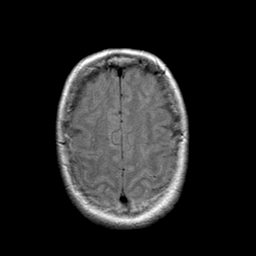

Stroke: proton density-weighted MR #1 -- Slice #20

[Home][Help][Clinical] Slice 20